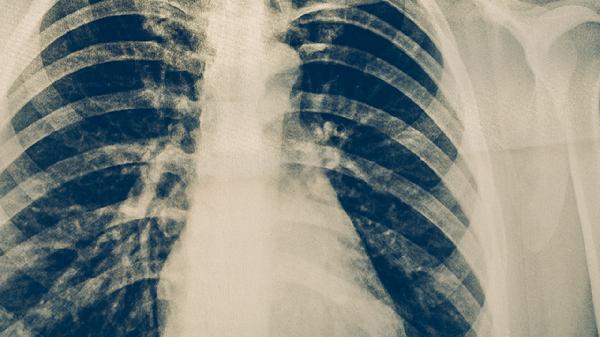

4、影像学表现

胸部X线检查中,肺炎多显示肺叶或肺段分布的斑片状阴影。肺结核典型表现为上肺野浸润灶伴空洞形成,慢性期可见纤维条索影和钙化灶。CT检查能更清晰显示结核树的树芽征和卫星灶等特征性改变。